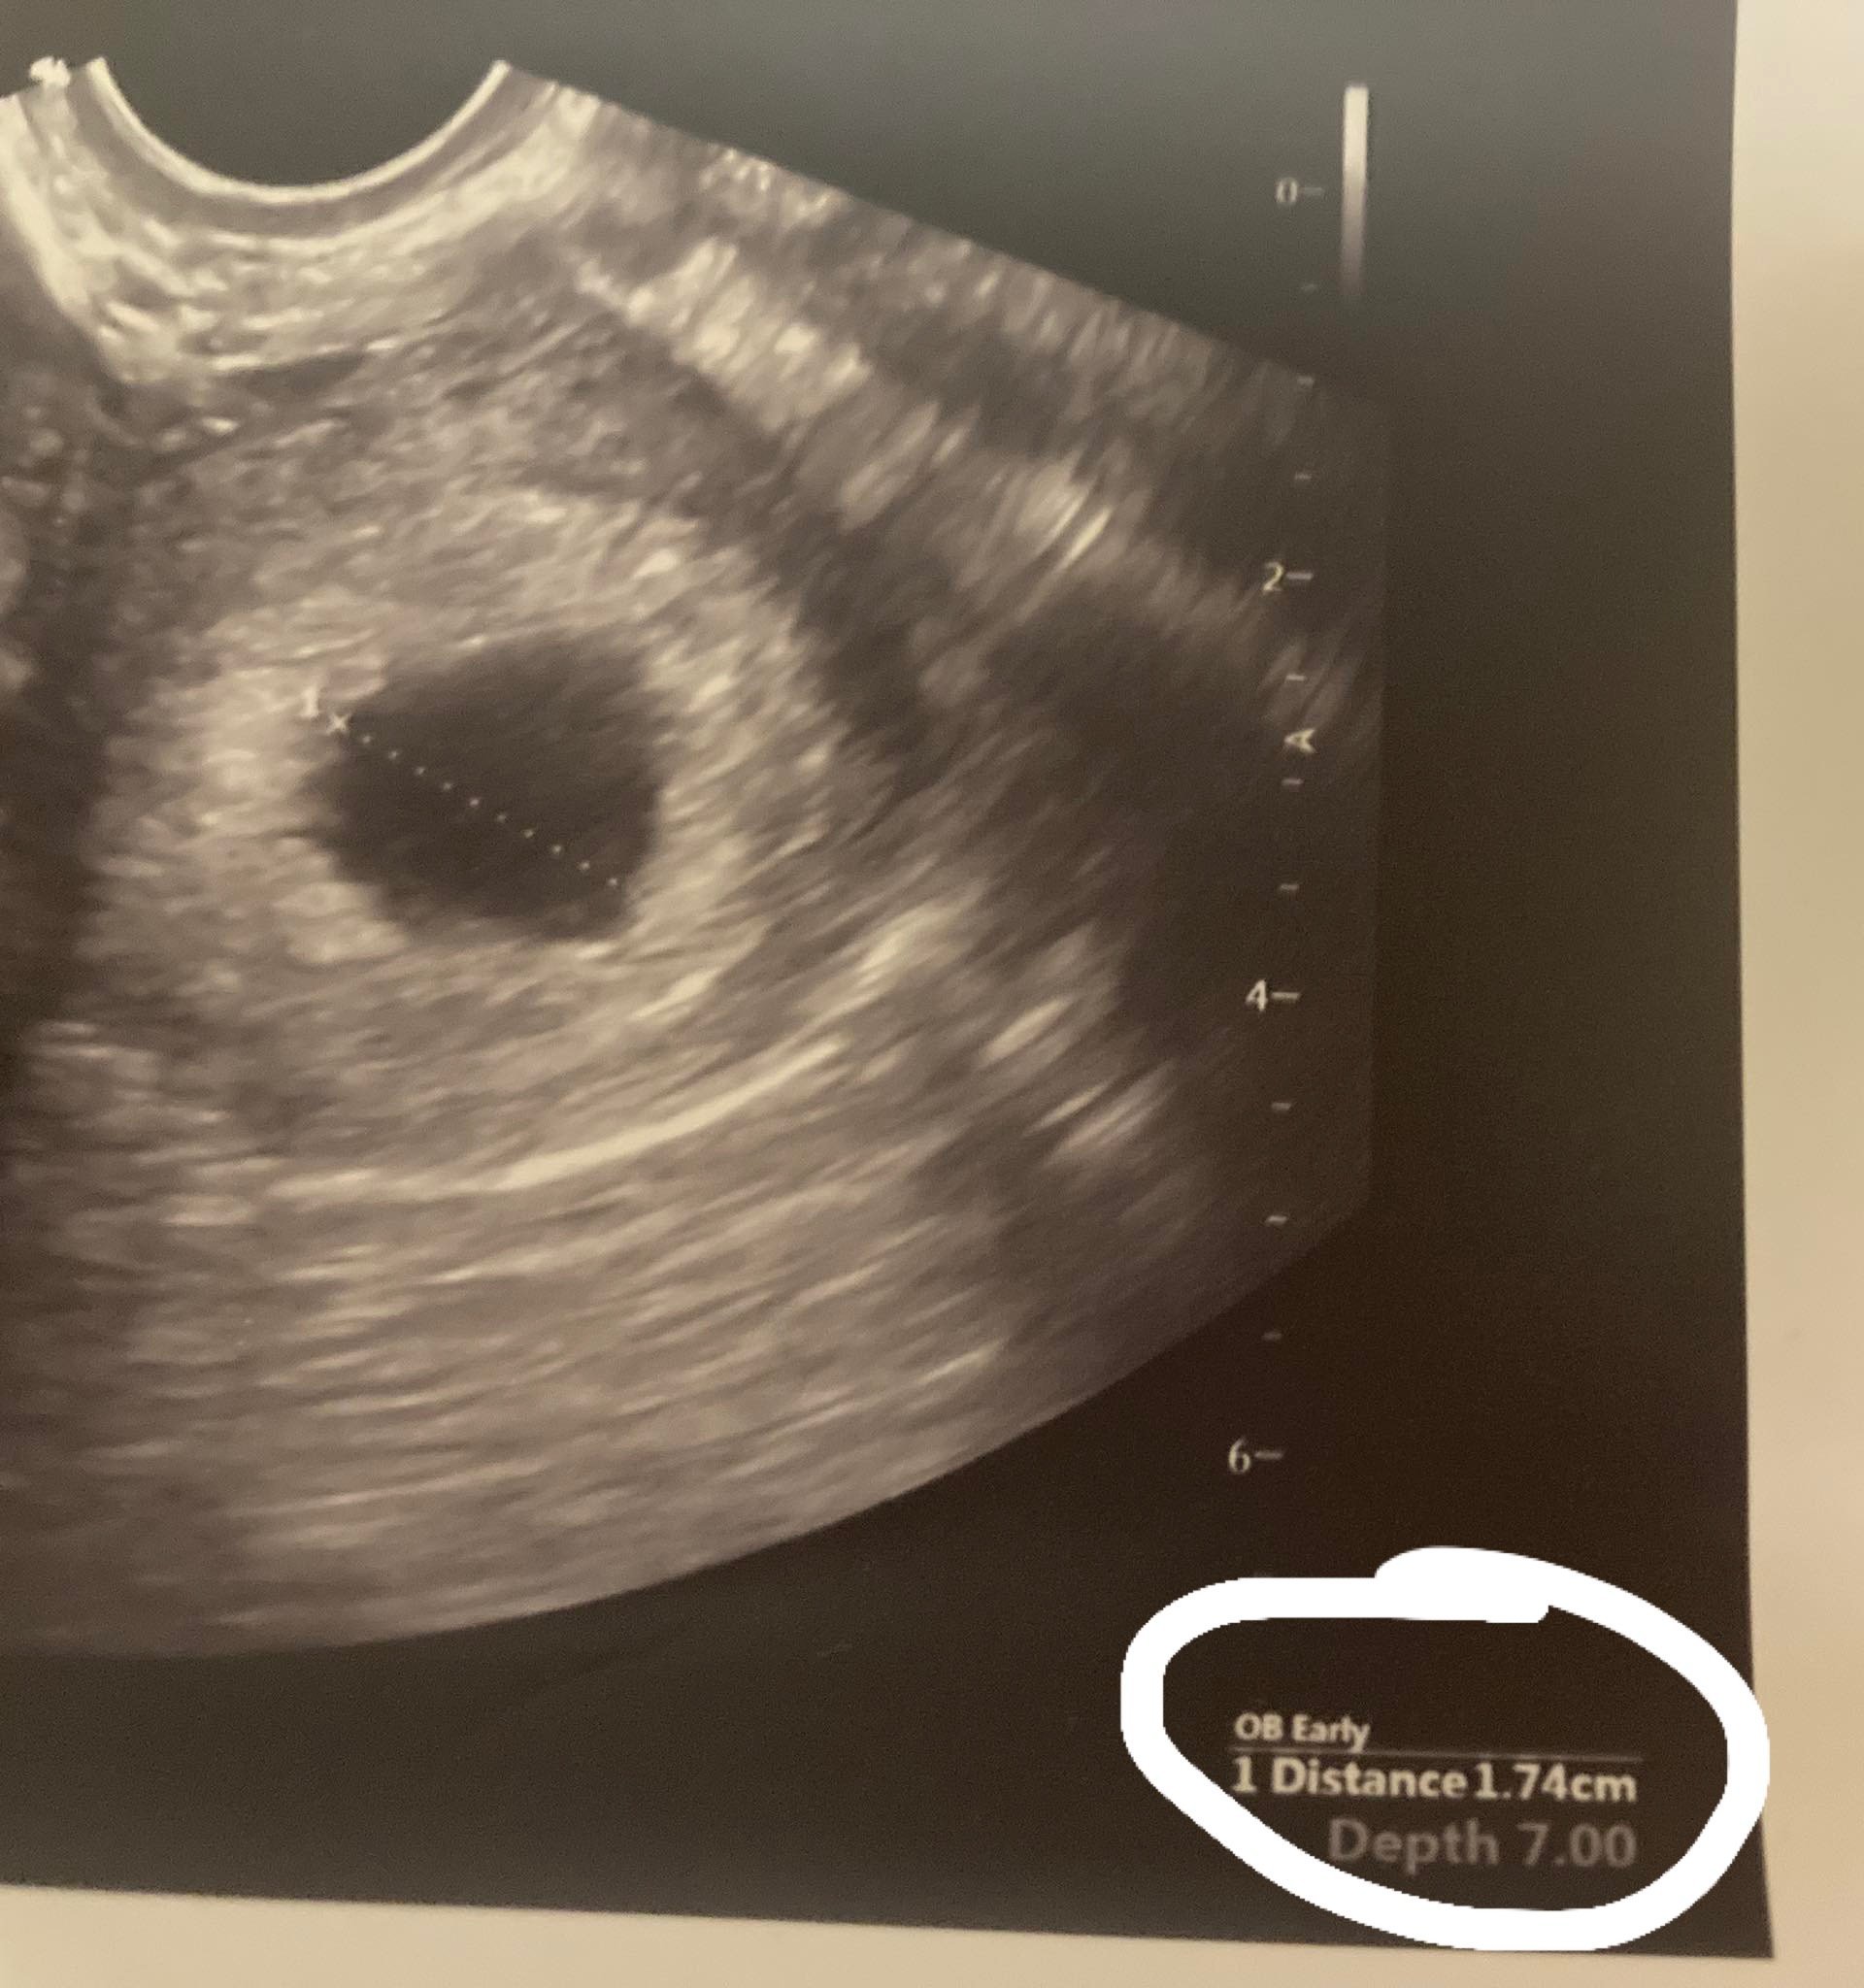

Какво означава, когато лекарят каже, че сакът е много малък и не отговаря?